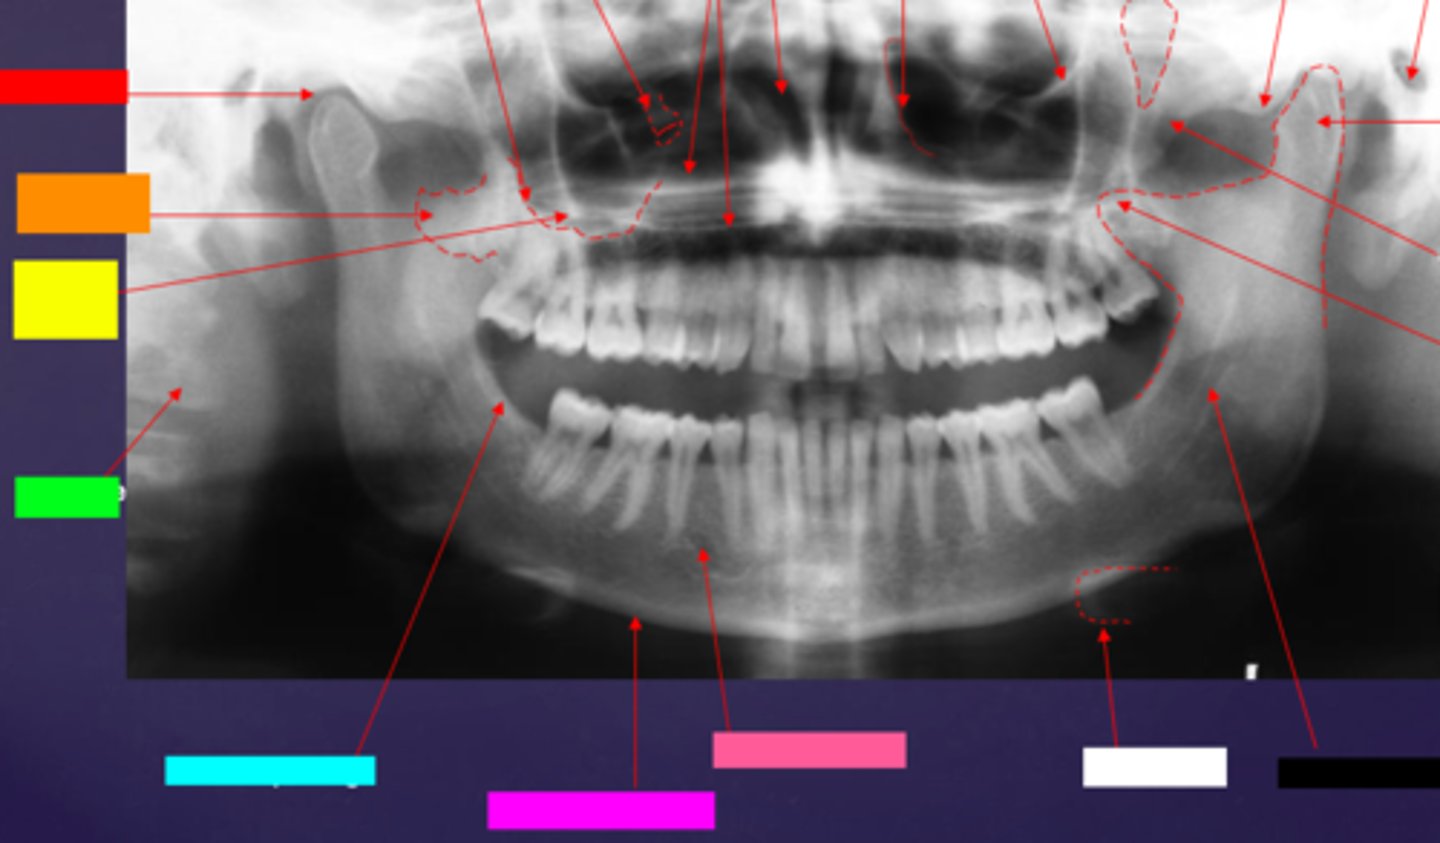

ID the soft tissue anatomy indicated by the arrow pointing from the red box:

ala of nose

ID the soft tissue anatomy indicated by the arrow pointing from the orange box:

nasal septum

ID the soft tissue anatomy indicated by the arrow pointing from the yellow box:

columna (the septum separating the nostrils)

ID the soft tissue anatomy indicated by the arrow pointing from the green box:

tragus

ID the soft tissue anatomy indicated by the arrow pointing from the light blue box:

ear lobe